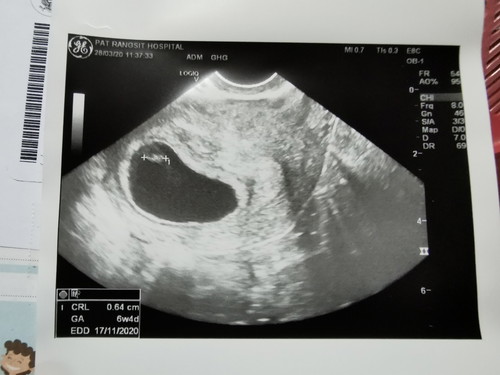

เราประจำเดือนขาดวันที่1มีค. เลยตรวจขึ้น2ขีดก้อเลยไปฝากท้องวันที่27มีค. คุณหมอซาวทางมดลูกแล้ววัดขนาดบอกว่าขนาดตัวของลูก 0.64ค่ะ อายุครรภ์ 6สัปดาห์4วัน แต่บอกว่าไม่เห็นหัวใจลูกเราโดยบอกว่าปกติต้องมีชีพจรแล้วต้องเห็นการเต้นหัวใจแล้ว เราเลยใจคอไม่ดีอะคะ